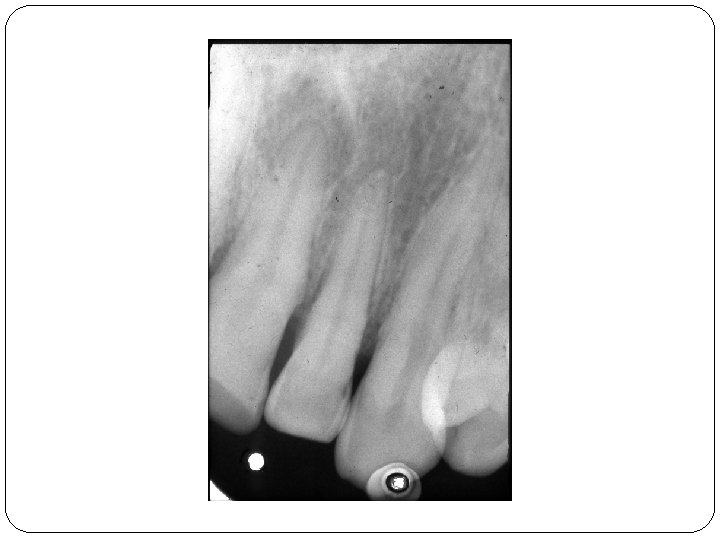

I. Akute Apikale Parodontitis � PRIMER Symptome: Akute Entzündung in der Umgebung der Wurzelspitze. Dauerschmerz in der Umgebung des Zahnes, Perkussionsschmerz, Der Patient hat das Gefühl, der Zahn sei länger geworden. Ursache: Pulpitis, Trauma, Caries, Wurzelbehandlung Röntgen: Im Röntgenbild bietet die primär-akute apikale Parodontitis zunächst keine Veränderungen. Nach einigen Tagen wird der durch die Entzündung ausgelöste Knochenabbau als diffuse Aufhellung in der Umgebung der Wurzelspitze erkennbar. + Periodontale Spalt ist breiter. � SEKUNDER Symptome: Akute Exazerbation einer primär-apikalen Parodontitis. Röntgen: Ähnlich wie chronische apikale Parodontitis

I/A Periodontitis periapicalis acuta �Acuta Wurzelhautentzündung �Symptome: spontaner Zahnschmerz, Perkussionsschmerz �Röntgen: Keine Veränderung oder periodontale Spalt ist breiter.